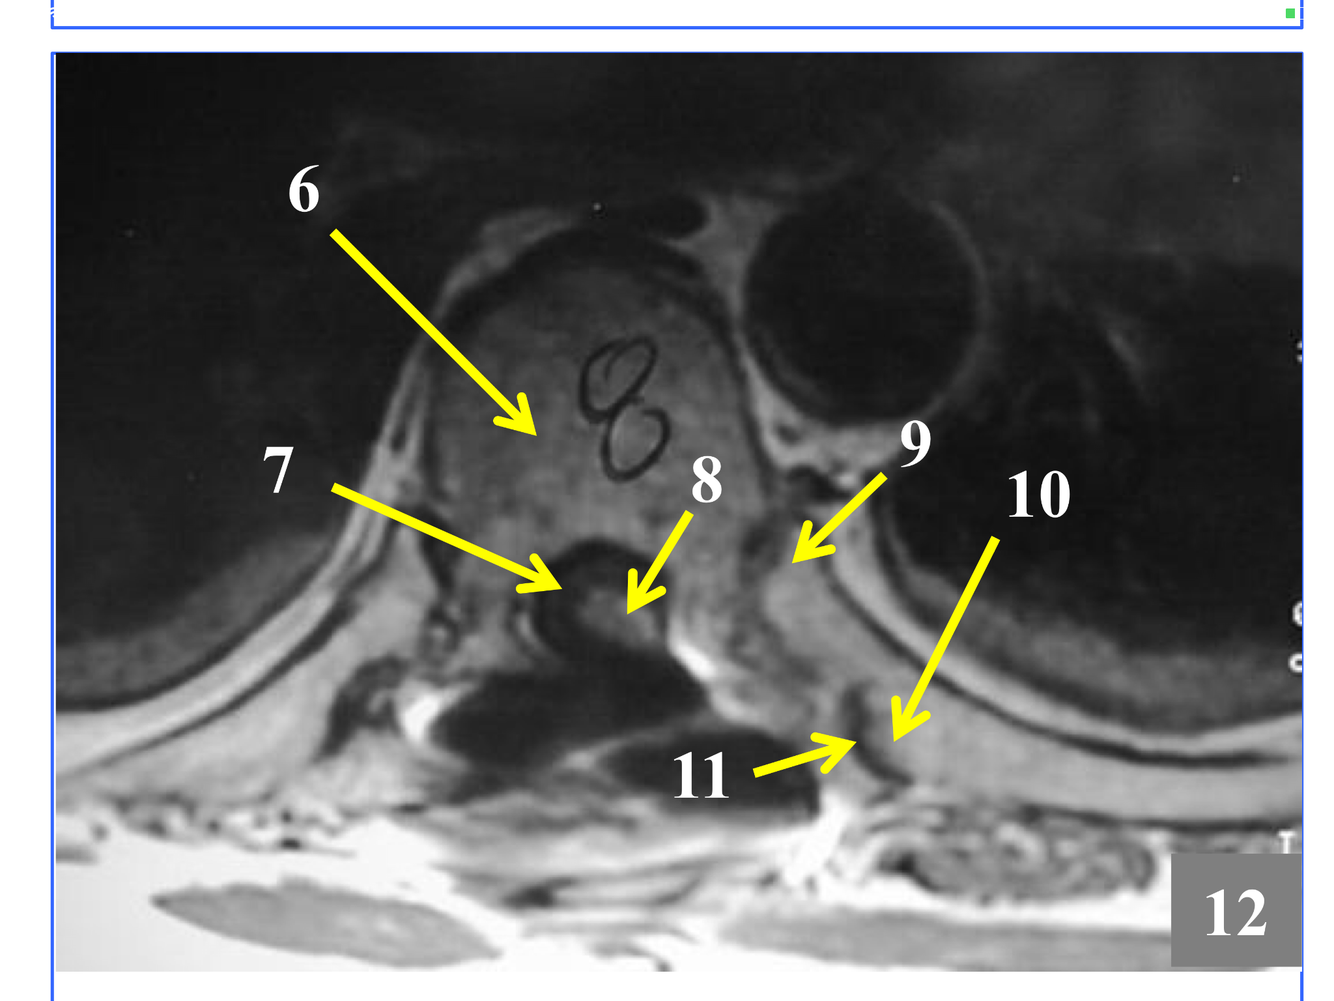

*near the atlantooccipital joint

**the tubercle of the anterior arch is where teh arrow is pointing, but not seen here.

* Just superior to atlantoaxial joint

* The stack of inferior and superior articulating processes, and the zygapophyseal joints they form